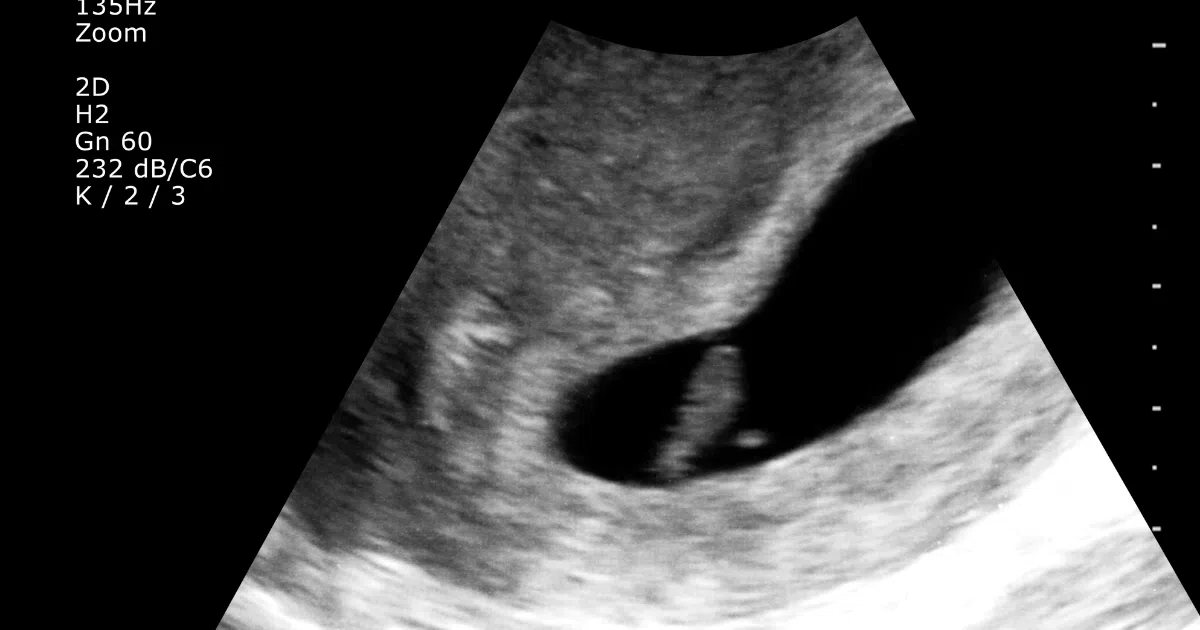

Below is an example of the Ramzi method being used on the transvaginal ultrasound image of a baby girl.

Ramzi Theory – Girl Example

In this transvaginal ultrasound scan image, the placenta is on the left side- meaning, according to the Ramzi method, it is a girl!